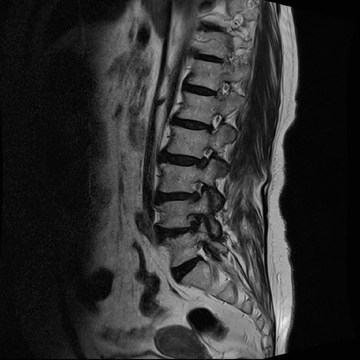

요추 협착증 수술 전·후

2020.08.30

2022.09.06

ㆍ환자 동의를 받은 자료이며, 이미지 사진은 실물과 다를 수 있습니다.

ㆍ모든 자료는 새움병원 자료입니다.